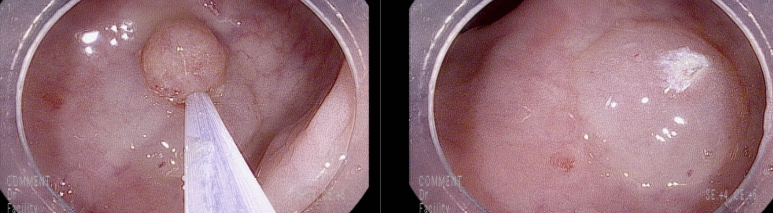

대장내시경 8 mm의 경을 가지는 용종이 직장하부에서 관찰되어 용종절제술로 제거함, 표면은 발적이 있으며 지저분한 염증성 양상임

단일 연소성 용종의 치료는, 다발성 용종증과 달리 재발 및 악성 변화 가능성 변화 가능성이 거의 없음에도 불구하고, 출혈 등의 증상을 해결하고 선종 동반 여부 등의 정확한 진단을 위해 절제를 통해 제거되어야 한다. 선암

으로의 악성변화가 보고되고 있고, 선종으로 변화하거나 선종과 공존할 수 있는 가능성이 있으므로 조직소견에서 이형성이나 선종 변환이 보이는 경우는 추적 검사가 필요하다.